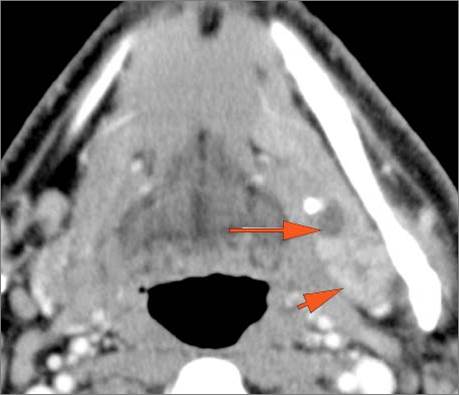

30-year old male with left facial swelling and tenderness mainly in the submandibular space. Primary clinical suspicion was an odontogenic infection.Exam

CT: Contrast- enhanced CT of the maxillofacial region and neck and related anatomy with images obtained in the balanced or venous vascular phase to ensure optimal visualization of both arterial and venous structures as well as possible reactive changes around infected collections. 0.5-3.0 mm thick sections were obtained in the axial plane and reformatted 3D and/or in the coronal and sagittal planes and viewed inter actively in 3 dimensions at the computer work station.